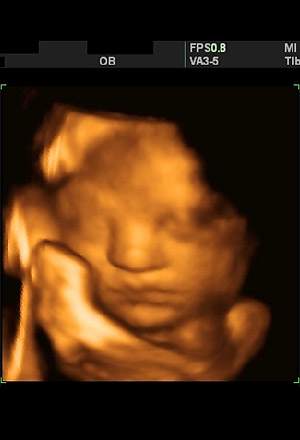

Month 8 (Week 32)

The baby has put on quite some weight since last month, mostly fat and muscle tissue, and now weighs about 1.7 kilograms (3.8 pounds) and measures 42 cm (16.7 inches) long. It will gain up to half its birth weight between now and delivery. The baby's irises can now dilate and contract in response to light and it can open or shut its eyes at will. The baby urinates about half a liter of urine into the surrounding amniotic fluid daily.